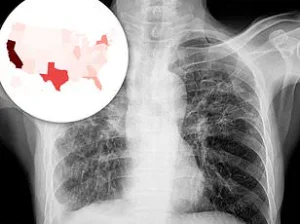

The Centers for Disease Control and Prevention (CDC) reports that the number of TB cases in the United States fell steadily from 1993 until 2020, when the country recorded its lowest number of cases in over two decades—7,170.

However, a troubling reversal began in 2021, with cases surging to 7,866, marking the first significant increase in more than a quarter of a century.

The upward trend has continued unabated.

Provisional CDC data from 2024 reveals a record high of 10,347 TB cases, an 8% increase from the previous year and the highest number since 2011.

This rise has sparked concern across the nation, as 80% of U.S. states now report increasing TB rates.

Demographic patterns have also shifted significantly over the past two decades.

In 2001, the CDC first recorded a majority of TB cases among non-U.S. born individuals, a trend that has since persisted.

Immigrants and international travelers now account for the majority of infections in the United States, highlighting the role of global mobility in the spread of the disease.